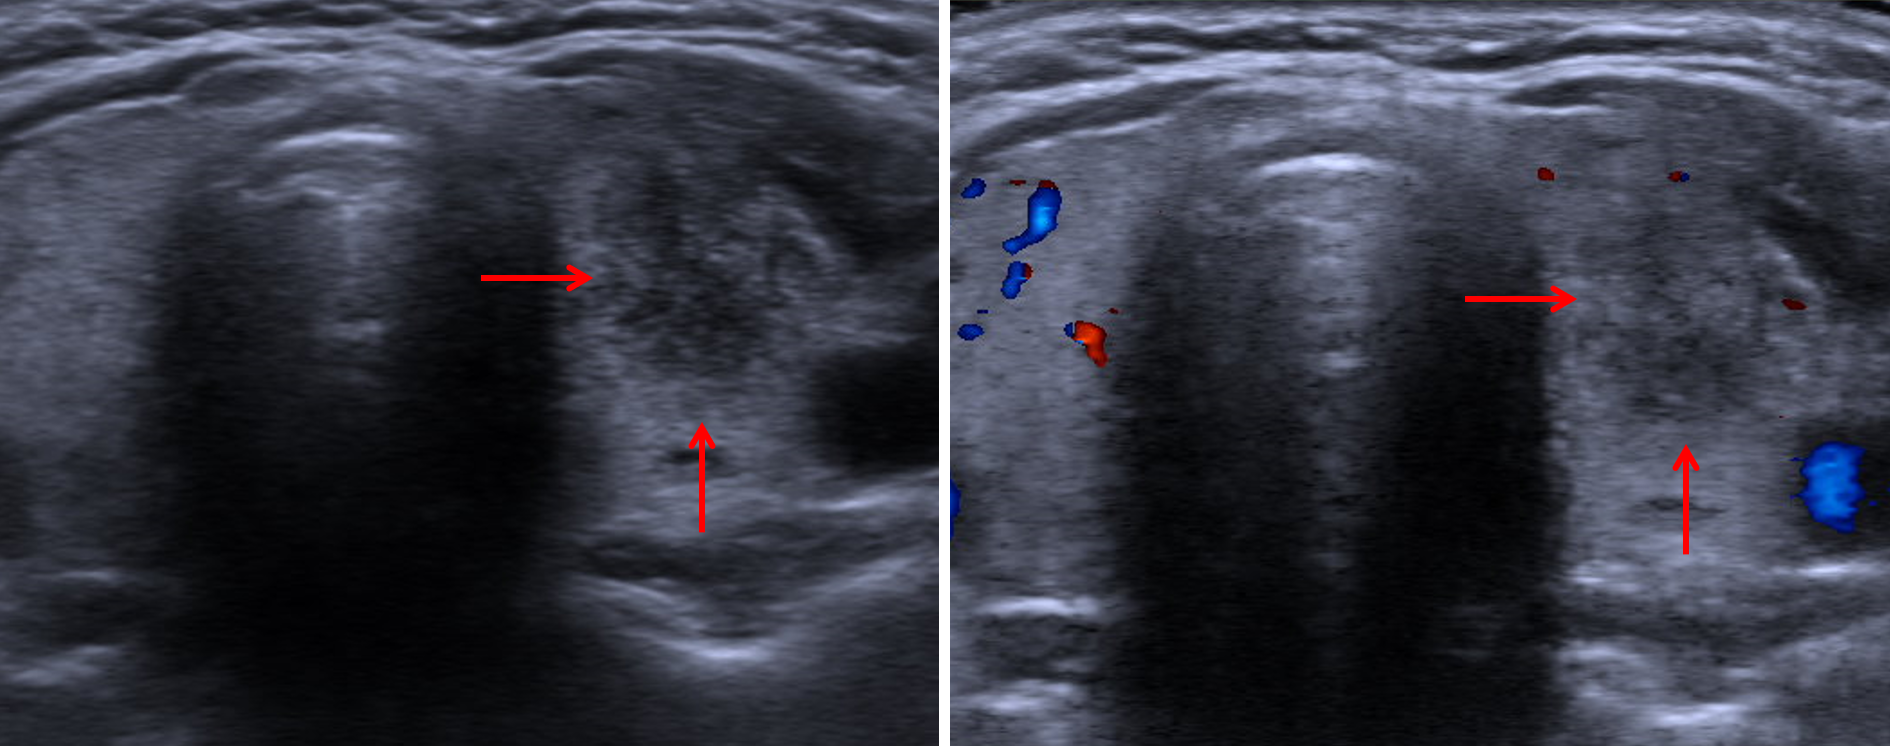

Age: 46

Sex: Female

Indication: Neck tenderness

Subacute thyroiditis

Sample ReportIll-defined nodule in the left thyroid lobe measuring up to 2.2 cm with decreased internal vascularity in addition to multiple additional subcentimeter nodules, which are favored to relate to subacute thyroiditis in this patient presenting with neck tenderness. Recommend followup ultrasound in 4-6 weeks to assess for improvement in findings.

Subcentimeter nodules inferior to the left thyroid lobe, which may represent reactive lymph nodes and can also be reassessed on followup imaging.